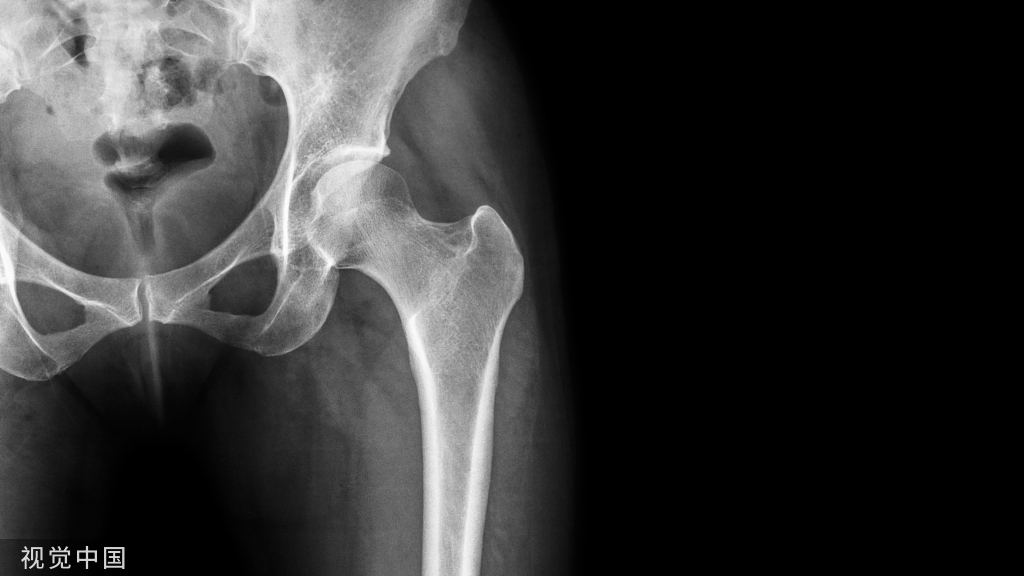

静脉血栓栓塞症(VTE)是骨科大手术围手术期的常见并发症,也是患者围手术期死亡及医院内非预期死亡的重要因素之一。

1.什么是静脉血栓栓塞症静脉血栓栓塞症(venous thromboembolism,VTE)是指血液在静脉内异常凝结,使血管完全或不完全阻塞而引起静脉回流障碍,从而导致相应的机体变化。

2.静脉血栓栓塞症的分类常见的类型包括深静脉血栓形成(deep veinthrombosis,DVT)和肺动脉血栓栓塞症(pulmonaryembolism,PE)。两者相互关联,是 VTE 在不同部位和不同阶段的两种临床表现形式。

DVT 是指血液在深静脉腔内异常凝结,阻塞静脉管腔,导致静脉回流障碍,引起远端静脉高压、肢体肿胀、疼痛及浅静脉扩张等一系列临床症状。血栓一旦脱落,随血流进入肺动脉,阻塞血管后会引起PTE的发生,轻者会出现呼吸困难、胸憋、气紧等症状,重者则会危及患者生命,出现致死性事件的发生。